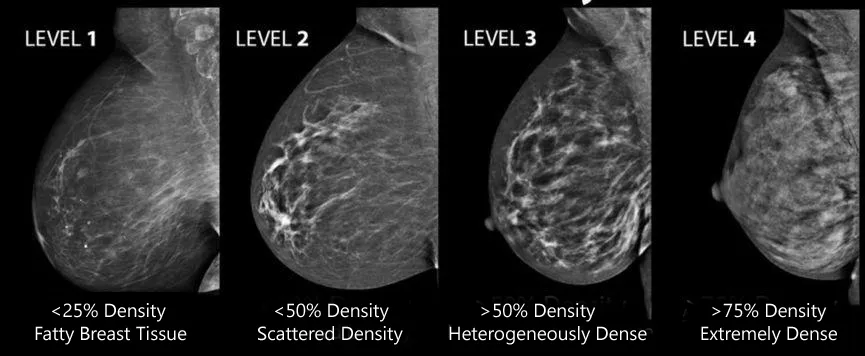

The third is breast density.

This is something most people don’t know. Studies have found that dense breasts are more likely to develop cancer. This isn’t a physical sensation, but rather a characteristic seen in medical imaging . Generally, breasts with less fat and more glandular tissue are more dense.

From left to right, the density increases. The leftmost breast contains a lot of fat and has the lowest density, resulting in many seemingly transparent areas on the image; while the rightmost breast is almost entirely glandular and has a very high density.

Therefore, it is not simply that having a larger cup size will increase your risk of breast cancer. If the breasts are mainly fat, then the risk does not increase.

Why is the incidence higher in people with dense breasts? It’s not entirely clear, but it may be related to the origin of breast cancer. As mentioned in the first issue, breast cancer typically originates in mammary ducts and acinar cells , not fat cells. Therefore, dense breasts, with their numerous glands , may harbor more cells that are likely to become cancerous.

Dense breasts also bring another problem, which is that it is difficult to detect tumors by X-rays , which makes screening more difficult and easily delays the opportunity for early intervention.